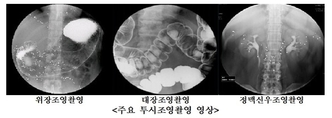

보건복지부는 진료정보교류 사업에 참여하는 의료기관이 1만332곳으로, 사업 시작 후 처음으로 1만곳을 돌파했다고 12일 밝혔다. 진료정보교류 사업은 환자가 다니던 병원에서 새로운 병원으로 이동할 때 의료기관이 직접 진료기록을 확인하고 진료에 활용할 수 있도록 기관 간 환자 진료기록 공유를 돕는 제도다. 사업에 참여하는 병원들은 환자 동의하에 진료기록과 과거병력, 투약 내역 등을 교류한다. 환자가 진료정보교류 홈페이지나 나의건강기록 앱에서 사업 참여에 동의하면 병원을 바꿀 때 새롭게 진료기록을 직접 제출하지 않아도 된다. 지난 한 해 동안 진료정보교류 시스템을 통해 공유된 진료정보는 영상정보를 포함해 약 181만 건으로 역대 최고 수준이다. 사업에 참여하는 기관은 1만곳을 넘겼으나 컴퓨터단층촬영(CT)·자기공명영상(MRI) 등 영상정보까지 공유할 수 있는 의료기관은 약 600곳에 불과하다. 영상정보 공유를 위해서는 전자의무기록(EMR) 시스템과 의료영상저장전송시스템(PACS)에 추가적인 개선이 필요해 의료기관의 참여가 다소 더디다고 복지부는 설명했다. 복지부는 진료정보교류 사업을 의료현장 전반에 확산하고 실제 진료에서의 활용도를 높이기 위한 개선을 추진하기로